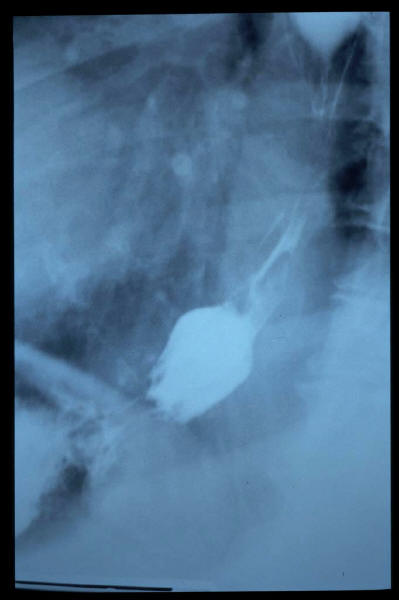

Hernia de hiato por deslizamiento al TGED.